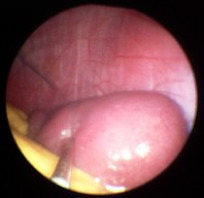

Milzbiopsie bei Sarkoidose